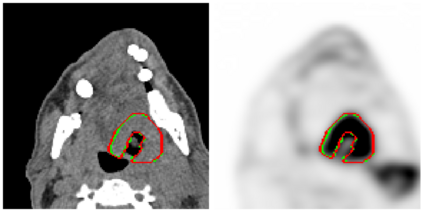

This paper presents an overview of the second edition of the HEad and neCK TumOR (HECKTOR) challenge, organized as a satellite event of the 24th International Conference on Medical Image Computing and Computer Assisted Intervention (MICCAI) 2021. The challenge is composed of three tasks related to the automatic analysis of PET/CT images for patients with Head and Neck cancer (H&N), focusing on the oropharynx region. Task 1 is the automatic segmentation of H&N primary Gross Tumor Volume (GTVt) in FDG-PET/CT images. Task 2 is the automatic prediction of Progression Free Survival (PFS) from the same FDG-PET/CT. Finally, Task 3 is the same as Task 2 with ground truth GTVt annotations provided to the participants. The data were collected from six centers for a total of 325 images, split into 224 training and 101 testing cases. The interest in the challenge was highlighted by the important participation with 103 registered teams and 448 result submissions. The best methods obtained a Dice Similarity Coefficient (DSC) of 0.7591 in the first task, and a Concordance index (C-index) of 0.7196 and 0.6978 in Tasks 2 and 3, respectively. In all tasks, simplicity of the approach was found to be key to ensure generalization performance. The comparison of the PFS prediction performance in Tasks 2 and 3 suggests that providing the GTVt contour was not crucial to achieve best results, which indicates that fully automatic methods can be used. This potentially obviates the need for GTVt contouring, opening avenues for reproducible and large scale radiomics studies including thousands potential subjects.